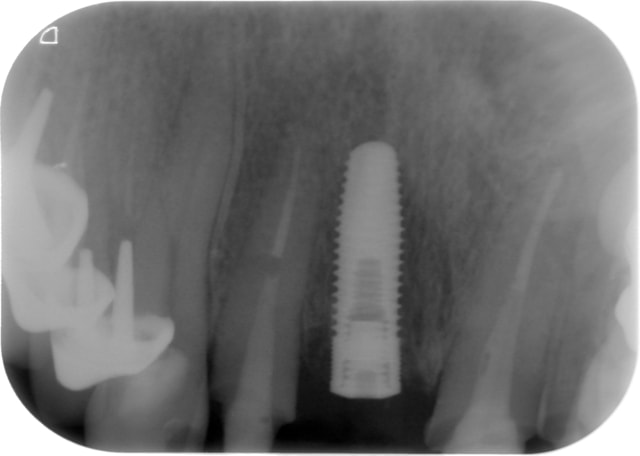

NB: sur les dents voisines on voit des provisoires réalisées le jour même pour me guider dans le positionnement tridimensionnel de l'implant, en aucun cas ce ne sont les provisoires d'usage.)

pour l'implant sur 11, ce jour:

pas de douleur

-pas de mobilité

-gencive " propre"

je vous laisse les clichés.

sur les photos, la gauche et la droite sont inversées

Super si la 13 est en cause, cela ne remet pas en question ton plan de traitement. D 'autant plus que sur ton premier cliché , la 12 ne semble pas fracturée, temporise , si tout s'estompe,

c'est O.K. Impec. D ' autant plus que je trouvais ton implant super bien placé. Attend un peu avant de déposer le tenon de la 12.